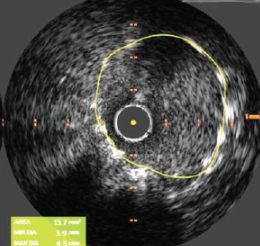

We then deployed a 4.0 mm x 24 mm Synergy Megatron stent (Boston Scientific) covering the ostium of the LMCA to the proximal LAD. The mid LAD was treated with 2.75 mm x 15 mm Resolute Onyx stent (Medtronic) deployed just distal to the take-off of the first diagonal branch, with a good final result (Figure 5). Post-stent IVUS demonstrated a minimal stent area of 5.4 mm2 within the mid-LAD stent and 13.7 mm2 within the LMCA (Figure 6).